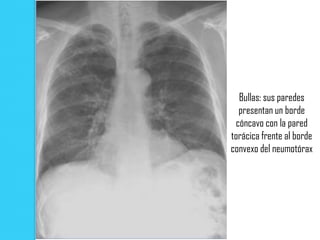

Bullas: sus paredes

presentan un borde

cóncavo con la pared

torácica frente al borde

convexo del neumotórax

Bullas: sus paredes presentan un borde cóncavo con la pared torácica frente al borde convexo del neumotórax